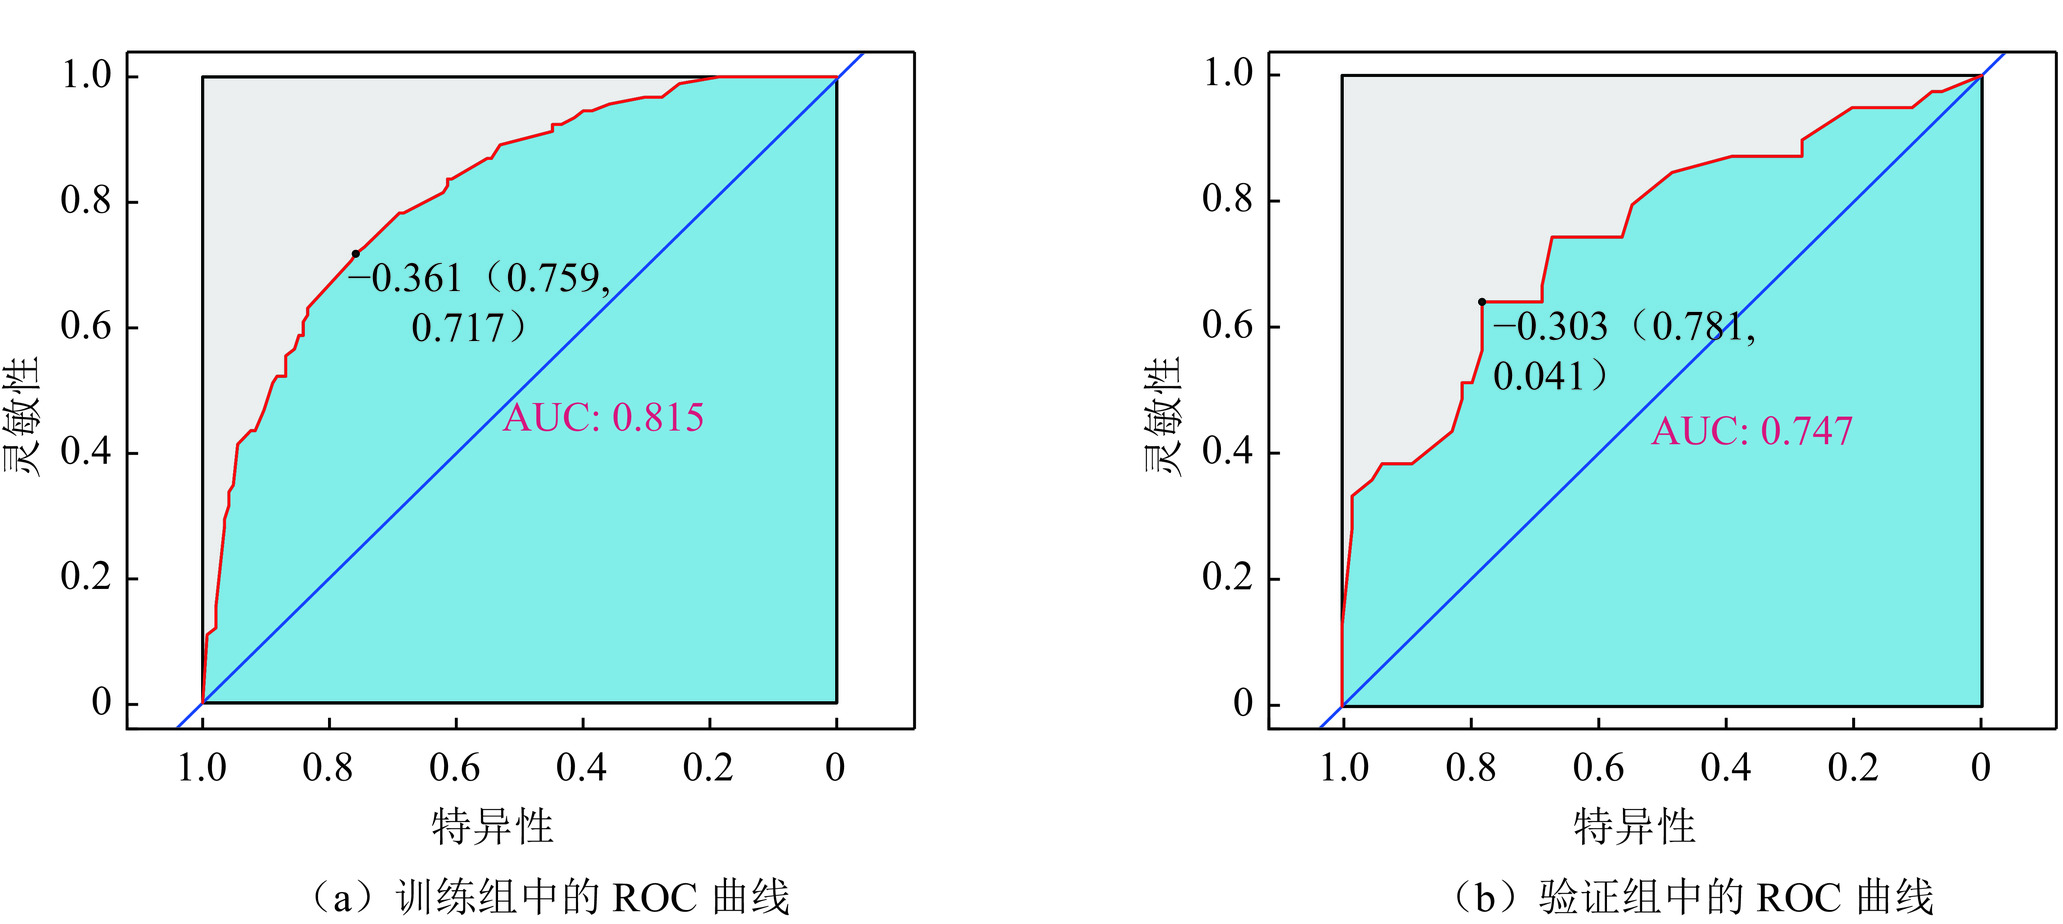

表 3 340例PTC患者CLNM的多因素logistics回归分析Table 3. Multivariate logistic regression analysis for CLNM in 340 patients with PTC变量 估计值 标准误 统计检验 Z P 截距 −2.596 0.688 −3.773 0.000 年龄(> 55) −0.755 0.332 −2.272 0.023 性别(女) −0.993 0.362 −2.739 0.006 边缘(不规则) 1.153 0.390 2.856 0.003 最大径(>10 mm) 1.051 0.362 2.898 0.003 构成(囊实性) 0.343 0.397 0.863 0.388 被膜接触 < 25% 1.791 0.622 2.879 0.004 25%~50% 2.005 0.623 3.217 0.001 > 50% 2.520 0.632 3.984 0.000 钙化 ≤3 mm 0.003 0.350 0.008 0.993 > 3 mm 0.515 0.591 0.871 0.384 340名PTC患者以7∶3随机分成训练组(n=273)和验证组(n=103),IRFs在随机分组中的差异无统计学意义(表4)。依据IRFs在多因素Logistic回归分析中的权重,在训练组构建列线图(Nomogram)(图1),并在验证组验证。结果显示,Nomogram的受试者操作特征曲线(receiver operating characteristic curve,ROC)在训练组的曲线下面积(area under the curve,AUC)为0.815(95% CI:0.761~0.870),在验证组中的AUC值0.747(95% CI:0.646~0.848)(图2)。Nomogram预测个体患者CLNM发生概率的实例演示如图3。

图 3 Nomogram预测CLNM的性能演示(界值为0.303)注:患者1,男性,44岁,PTC病例,CLNM阳性。CT平扫示右叶中下部类圆形病灶,内见钙化,与甲状腺被膜接触约75%(a),增强后不均匀强化(b),超声显示低回声区,境界清晰,边缘光整,约20.6×16.5×18.5 mm(c),对照Nomogram:男性(38分)+年龄 < 55岁(28分)+被膜接触 > 50%(100分)+最大径 > 10 mm(45分)=211分,对应的CLNM预测概率0.73。患者2,女性,37岁,PTC病例,CLNM阴性。右叶内不规则低密度结节,边缘与被膜无接触(d),增强后轻度强化(e),超声显示境界清晰,边缘不光整的低回声区,最大径约8.5 mm(f),对照Nomogram:年龄 < 55岁(28分)+边缘不规则(48分)=76分,对应的CLNM预测概率0.10。Figure 3. Performance of the nomogram for CLNM (cutoff=0.303)Nomogram的预测准确性和临床实用性用Calibration和DCA评价(图4和图5),Calibration显示预测概率和实际概率在训练组和验证组中一致性程度很高。DCA曲线表明,当个体患者预测概率在0.1到0.85范围内,Nomograms预测CLNM的净收益高于无预测组或全部干预组。